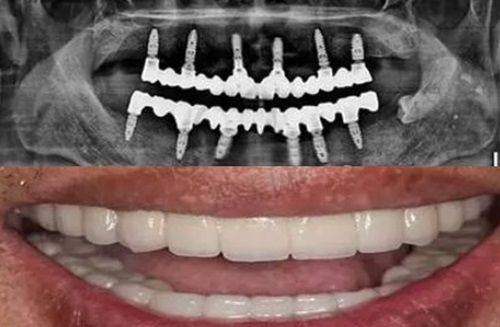

1. 种植牙中 心:引进国内外精良种植系统,配备数字化导板技术,实现精细微创种植。对于那些牙齿缺失的患者来说,种植牙是一种理想的修复方式。美益达口腔的种植牙中 心利用精良的技术,能够严谨地定位种植体的位置,减少手术创伤,缩短修复时间,让患者更快地修复咀嚼功能和美观。

任永先医生:专攻种植牙、牙周炎及复杂牙体治疗。在种植牙领域,任医生有着深厚的造诣,他熟练掌握各种种植牙技术,能够根据患者的口腔情况和身体状况,选择更合适的种植方案,确保种植成效的稳定性和持久性。对于牙周炎的治疗,任医生有着独特的见解和治疗方法,他能够采用综合治疗的手段,有效地控制牙周炎症,保护患者的牙齿和牙周组织。在复杂牙体治疗方面,任医生凭借不错的技术和丰富的经验,能够解决各种疑难的牙体问题,为患者保留更多的天然牙齿。